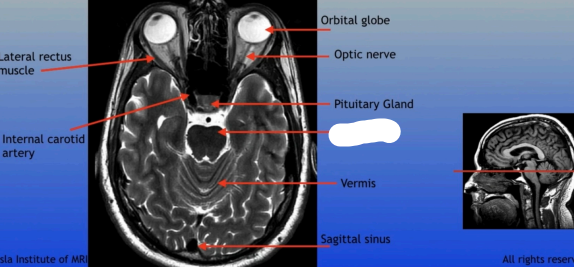

Lateral Rectus Muscle

Internal Carotid Artery

Orbital Globe

Optic Nerve

Pituitary Gland

Vermis

Sagittal Sinus